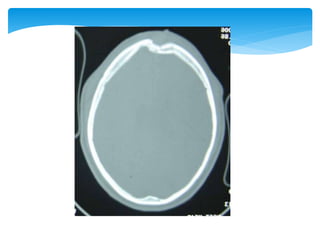

Approach To CTScanCT scan Bone window Look for fractures- •Cranial vault •Skull base •Facial bones Tissue window •EDH •SDH •ICH •Contusions •Pneumocephalus •Hydrocephalus •Cerebral edema Subdural window •Any hemorrhage •Soft tissue and bone •Fontanel •Suture lines •Foreign bodies

 Appearance ofthe normal structures CT Scan